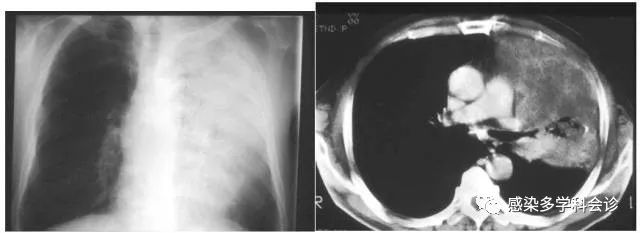

军团菌肺炎:大片实变+纤维化+变化快+重力效应+支气管壁增厚+胸腔积液+空洞及淋巴结肿大(免疫低下者)